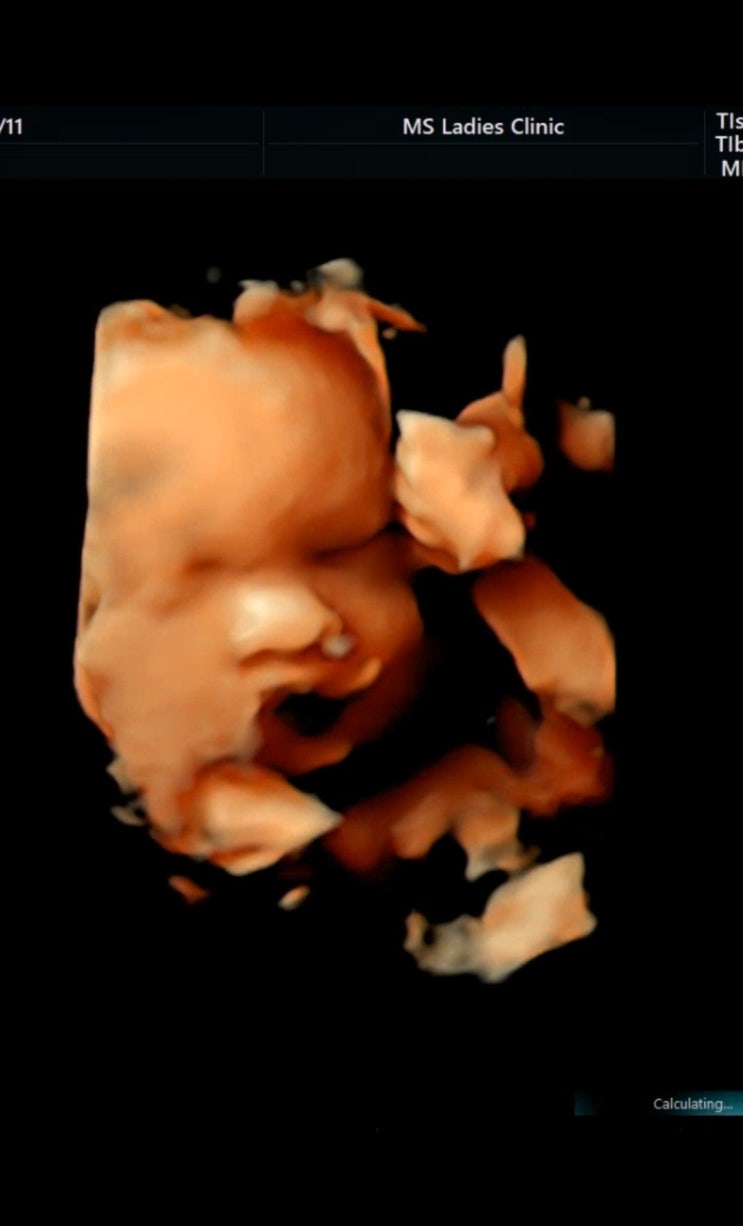

31주 정기검진 귀여운 용접이? 오늘은 얼굴도 나름 보여주고 벌써 볼살도 생겨짜나?!! 너무 귀엽짜나 ㅠ...